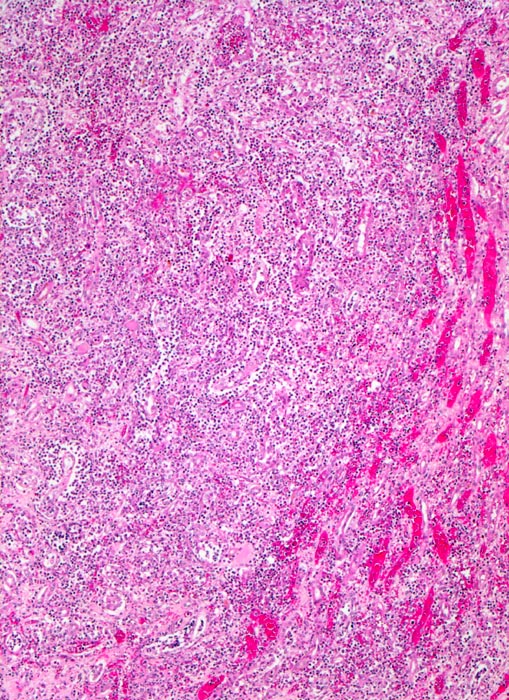

akute Pyelonephritis (destruktive interstititelle Nephritis)

Destruktives streifenförmiges granulozytäres Infiltrat. Die Tubuli sind nicht mehr erkennbar. Am Rand des Infiltrates hyperämische Gefässe (makroskopisch gelber Herd mit rotem Randsaum).

Uretero- und Nephrolithiasis

Fieber mit Schüttelfrost, Übelkeit und Flankenschmerzen. Dysurie. Exsiccose.

Histologie

50